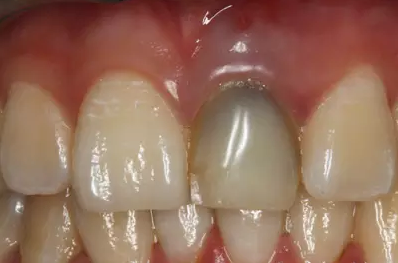

患者外院螺紋樁核加樹脂冠

X線片顯示螺紋釘出根管壁

唇側(cè)出現(xiàn)瘺管